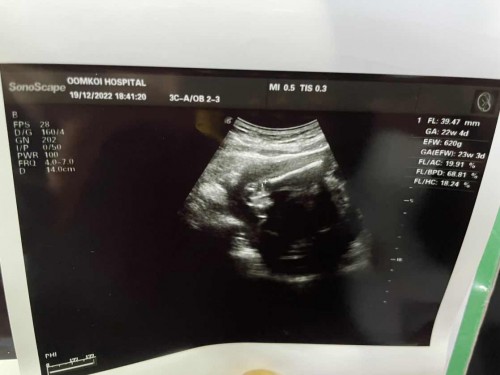

อยากสอบถามว่าภาพอัลตราซาวด์ 3 ภาพนี้คืออะไรค่ะ แม่ๆพอทราบไหมค่ะ คุณหมอให้มานะคะ

เป็นภาพอัลตราซาวด์ตอน 24W ค่ะ

ภาพแรก ที่เป็นเส้นขาวๆชัดๆ น่าจะเป็นกระดูกขาน้องค่ะ ภาพที่สอง น่าจะกะโหลกศีรษะน้อง ภาพที่สาม น่าจะเป็นช่องท้องค่ะแม่